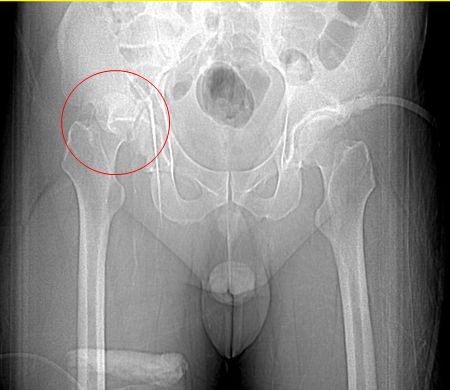

圖:手術治療前後的大腿股骨與髖關節。

而當時的主治醫師就是個性直率低調,被同事與後進同仁暱稱為鄺爺的骨科鄺世通醫師,這個在鄺醫師口中的小骨折,其實是包含髖關節、大腿股骨、膝蓋髕骨、與小腿脛骨等多處粉碎性骨折的複雜個案,不論是X光檢查,還是電腦斷層檢查,都能看見因為強力撞擊穿出髖關節的股骨,還有粉碎的髕骨,歷經數個小時的開刀,才救回洪國程先生的性命與右腿。